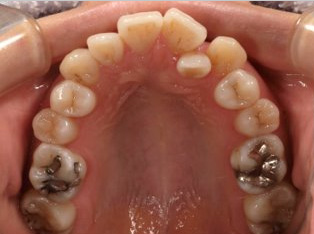

でこぼこがある状態になります。乱ぐい歯とも言われます。見た目がよくない審美障害が主な問題点ですが、その他にもでこぼこが多いことで、歯ブラシによる清掃性が悪くなり、結果、虫歯や歯周病のリスクも上がってしまいます。治療期間が短く済むことも多い為、気になった段階で早期に相談された方が良いと思います。

治療前

治療終了前